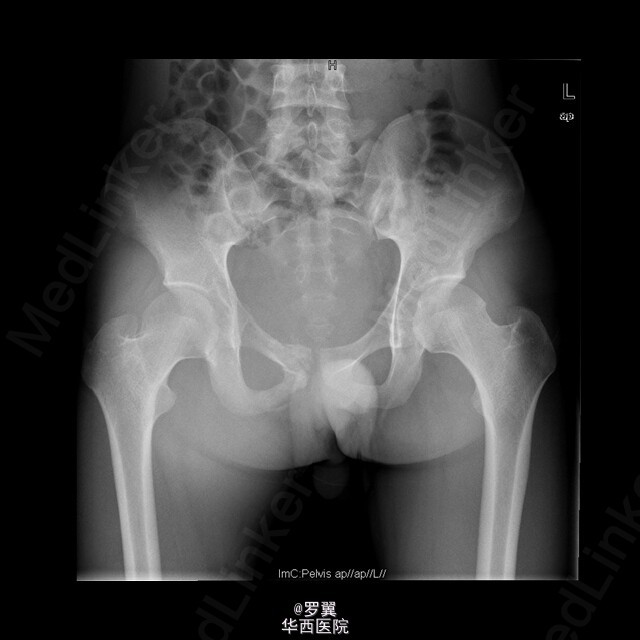

患者男,21岁,因“ 右髋疼痛7月伴右腹股沟包块2月”入院。查体:视:右腹股沟区可见一大小约15cmx10cm包块,未见浅表静脉怒张,无红肿及渗出,皮肤无破溃。触:质硬,边界不清,皮温稍高,局部深压痛。在右大腿根部前正中可扪及股动脉搏动。右侧鞍区感觉明显减退,右大腿上段内侧浅感觉减退。.肛门括约肌肌力Ⅲ级。动量:右髋伸90°,伸-10°。做伸直动作时患者包块区域疼痛加重。复查ct:盆腔巨大肿瘤,骨质破坏,考虑恶性肿瘤可能性大,核磁共振:考虑盆腔恶性肿瘤。入院后,完善相关辅助检查及术前准备,并采用阿霉素化疗方案化疗后,后在全麻下行腹主动脉球囊阻断下右侧骨盆肿瘤切除、腹股沟淋巴结清扫、人工组配式半骨盆置换术。术后1周即能拄拐下地,右髋能屈曲50°,右膝能屈曲65°。现出院。